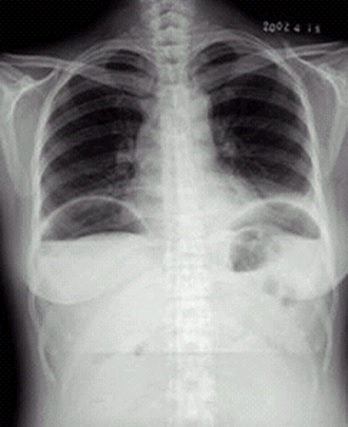

04卷-4.病史:女性,42歲,腹痛1天,進(jìn)行性加重。診斷

A.腸梗阻

B.腸結(jié)核

C.正常腹平片

D.消化道穿孔

題目解析:【該題針對“ X線-消化道穿孔 ”知識點(diǎn)進(jìn)行考核】